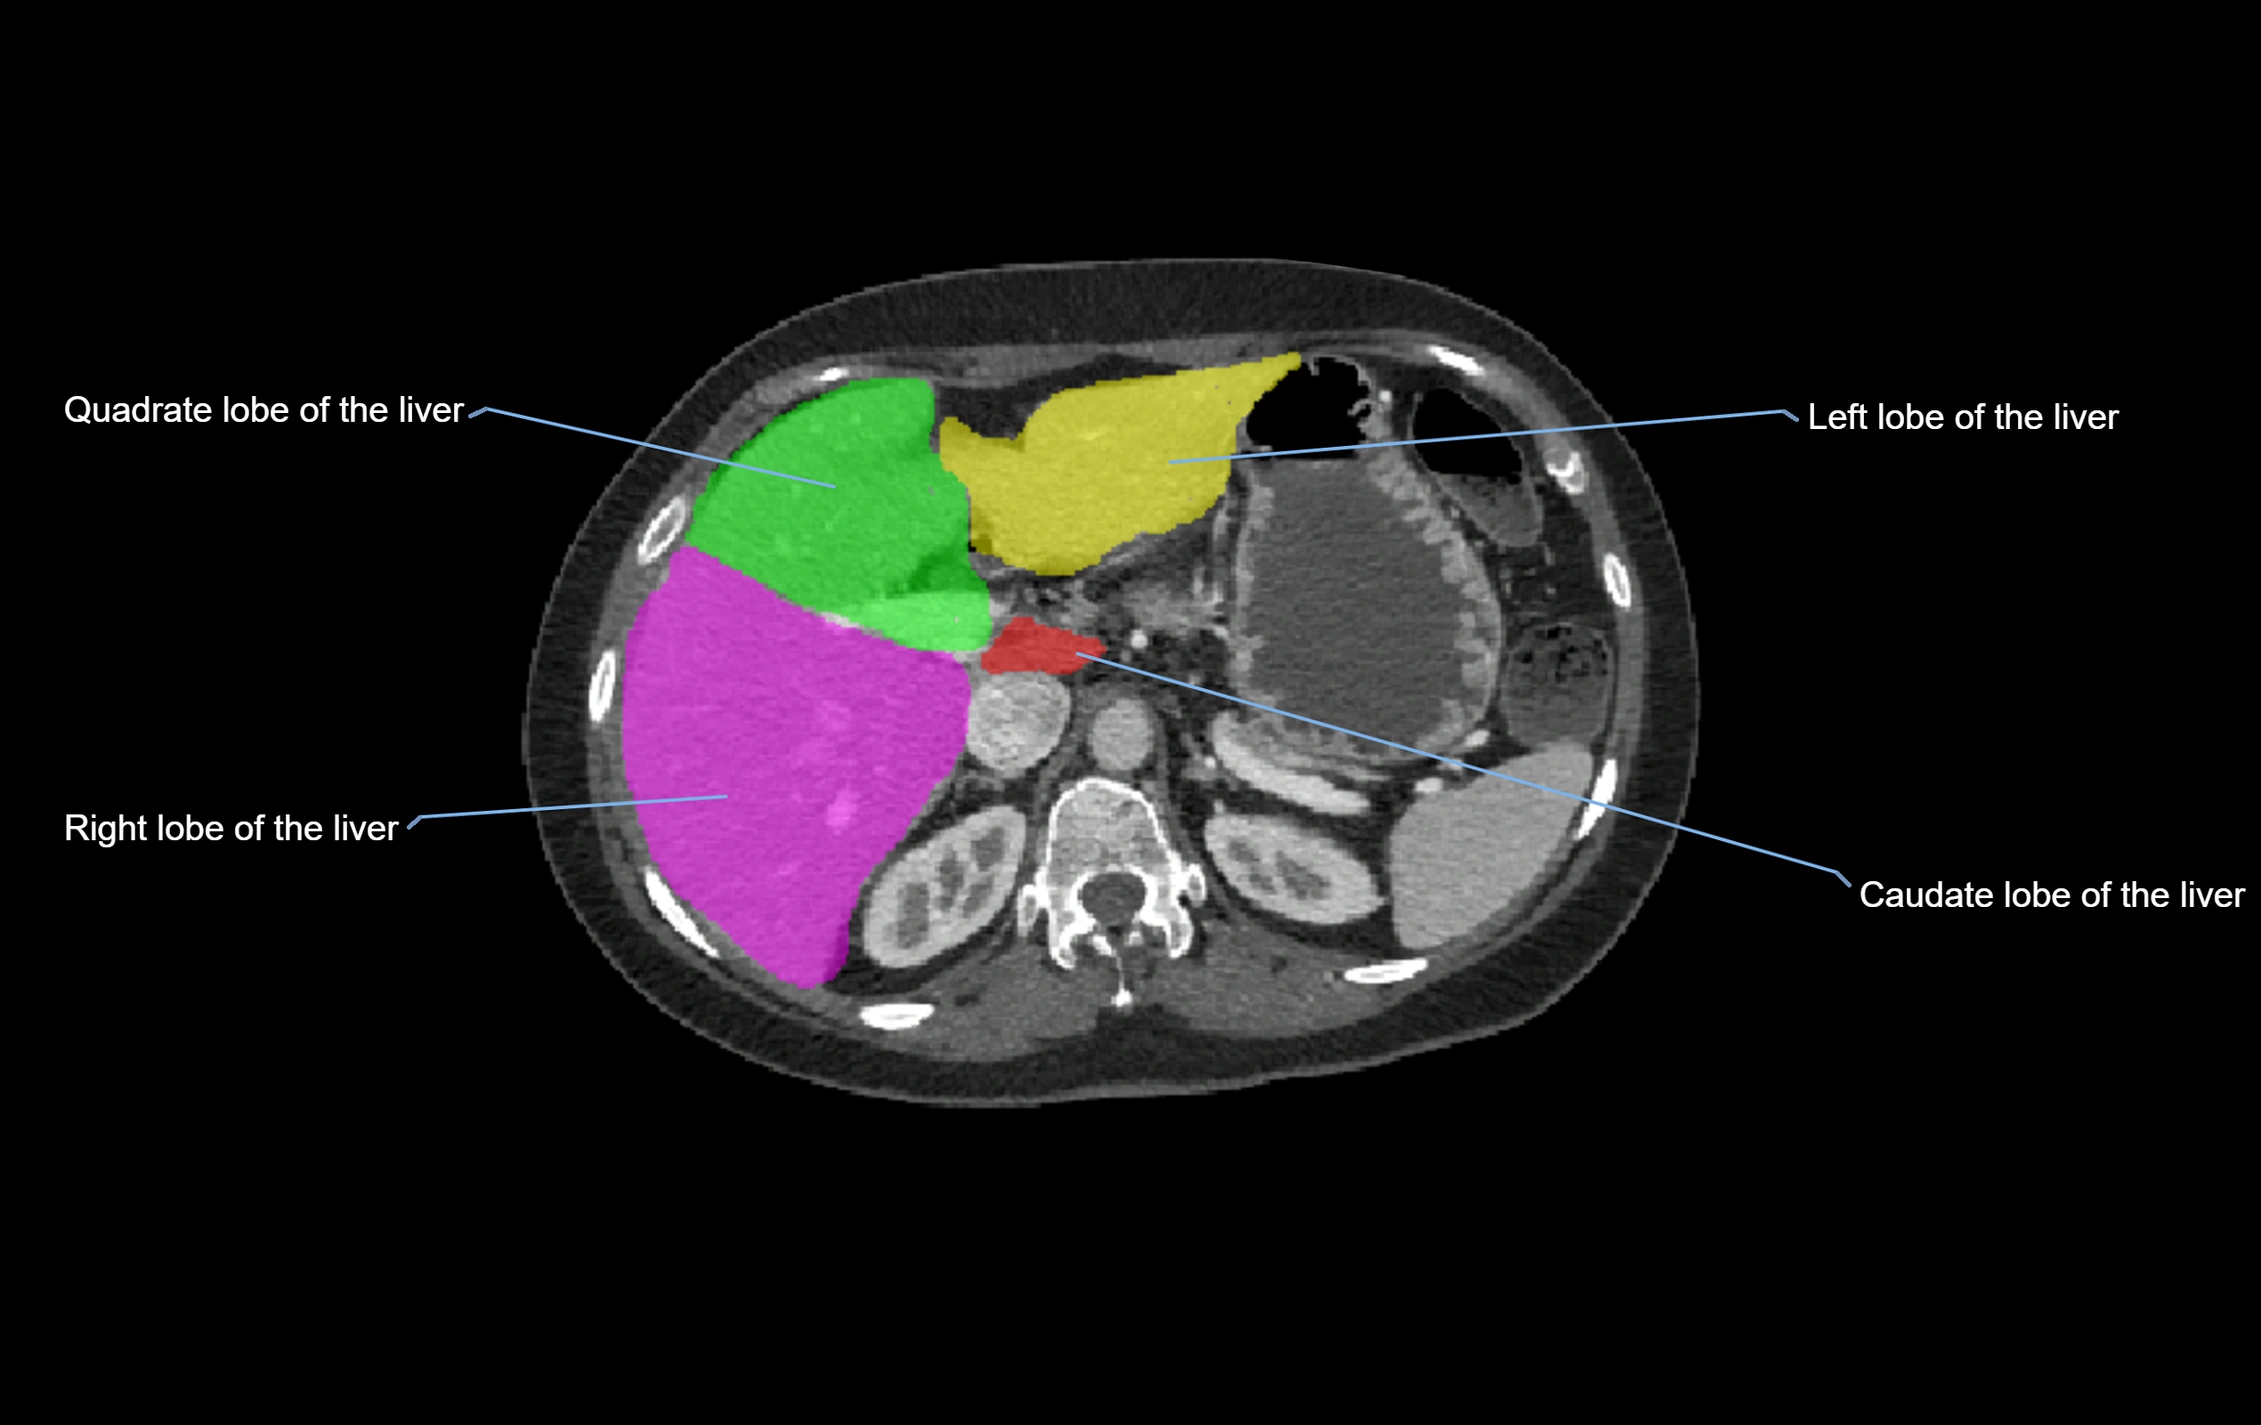

The caudate lobe of the liver is a distinct anatomical subdivision of the liver, designated as segment I in Couinaud’s classification. It lies on the posterior surface of the liver, between the fissure for the ligamentum venosum (left boundary) and the groove for the inferior vena cava (IVC) (right boundary). Superiorly, it is related to the posterior liver surface, and inferiorly it is separated from the left lobe by the porta hepatis.

The caudate lobe is unique because it receives dual portal venous and arterial inflow from both the right and left portal veins and hepatic arteries. It also has independent venous drainage directly into the IVC via multiple small hepatic veins, unlike other lobes that drain through the three main hepatic veins.

This anatomical autonomy makes the caudate lobe especially significant in liver surgery, transplantation, and hepatic venous outflow obstruction syndromes (e.g., Budd–Chiari syndrome). Enlargement of the caudate lobe is a characteristic imaging feature in chronic liver disease and cirrhosis.